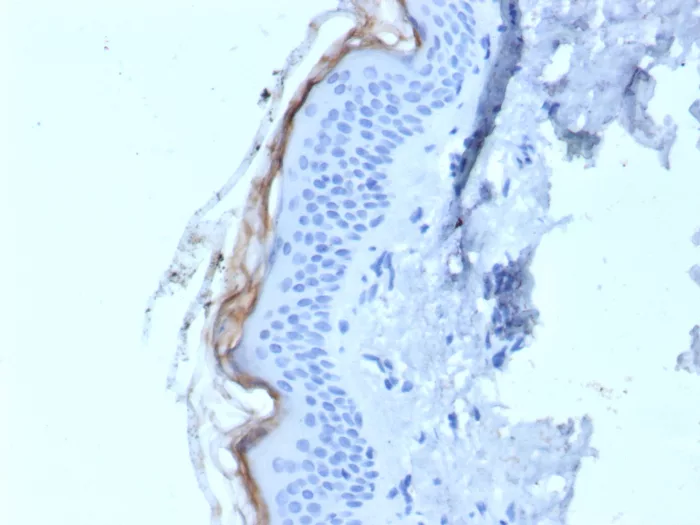

Immunohistochemistry (IHC)

1-2ug/ml

30 min at RT. Staining of formalin-fixed tissues requires heating tissue sections in 10mM Tris with 1mM EDTA, pH 9.0, for 45 min at 95°C followed by cooling at RT for 20 minutes

Human skin tissue (IHC). MCF-7 cell lysates.